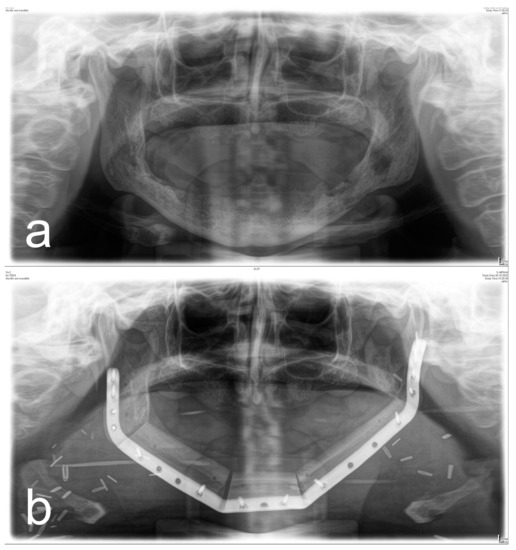

Figure 1, Figure 2, Figure 3 and Figure 4 illustrate two cases of advanced mandibular resection with severe hard and soft tissue injury followed by reconstruction using a vascularized fibula flap. This graft allows reconstruction of bone and soft tissue, the latter of which can be used to replace extraoral skin (Figure 2) or intraoral mucosa (Figure 4).

Figure 3. (a) Panoramic X-ray of a patient with extensive ORN of the mandible. (b) Postoperative panoramic X-ray of the same patient after ablative and reconstructive surgical therapy of ORN using a vascularized 3-segment fibula flap with an extraoral soft tissue transfer and a patient-specific implant.